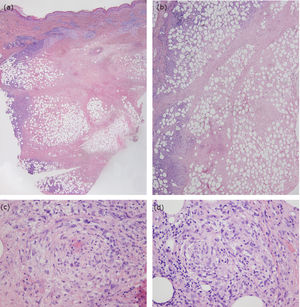

El estudio analítico, incluyendo autoanticuerpos, fue normal y la prueba de Mantoux y el test Interferon-Gamma Release Assay resultaron negativos. La ecografía Doppler no revelaba signos de trombosis o de tromboflebitis. El estudio histológico de una de las lesiones mostró, bajo una epidermis conservada y sin alteraciones, una necrosis amplia dérmica e hipodérmica, con un infiltrado inflamatorio de predominio linfocitario que afectaba a los septos y a los lobulillos del tejido celular subcutáneo, sin que se objetivaran linfocitos atípicos. Además, se observaron signos de vasculitis y escasos histiocitos y linfocitos formando granulomas (fig. 2). Los cultivos resultaron negativos. Con todo ello, el diagnóstico fue de vasculitis nodular.